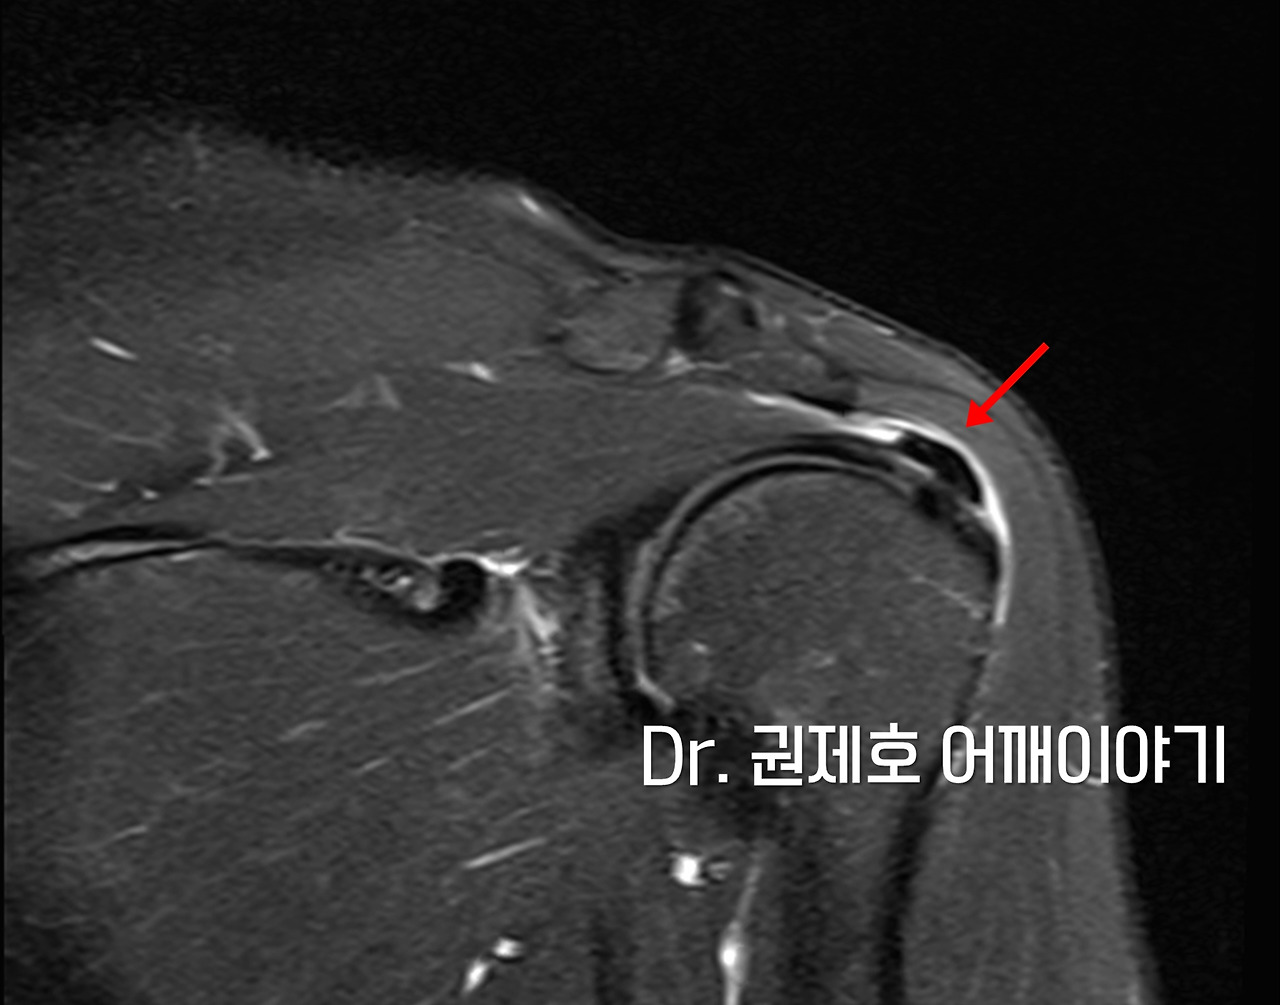

X-ray

외래에 왔을 때 엑스레이를 찍었다. 누가 봐도 어깨석회성건염이다. 그 크는 작지는 않았다.

MRI를 찍었다. 주사를 맞았음에도 힘들어하셔서 혹시 그 이상의 문제가 있진 않을까 검사했다. 석회주변으로 해서 염증이 가득 찬 소견이외에 석회가 어깨를 끊어지게 만들었거나 하는 소견은 관찰되지 않았다.